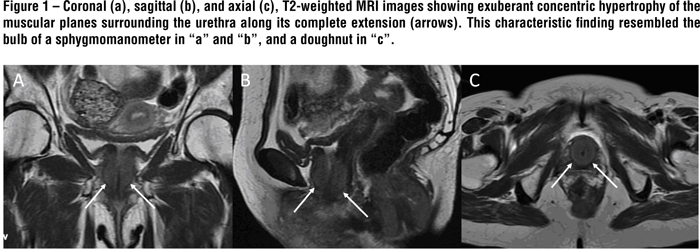

MRI revealed an exuberant concentric hypertrophy of the entire urethra. This characteristic imaging finding resembled a bulb of a sphygmomanometer on the sagittal and coronal planes, and a doughnut on the axial ones (Figure-1). The affected musculature was isointense on T1- and slightly hyperintense on T2-weighted images compared with unaffected muscles. The diffusion sequence showed restriction to free water molecules movements, making the hypertrophied muscles hyperintense on this sequence and hypointense on the ADC map (Figure-2). Additionally this patient also exhibited a marked concentric hypertrophy of the internal anal sphincter muscle, probably related to the same bladder neck neuropathological mechanism. This latter finding was previously misdiagnosed in another facility as a rectal tumor. After the intravenous contrast administration, there was slight enhancement of the hypertrophied muscle. The combination of the MRI findings together with the patient´s symptoms and urodynamic testing was consistent with the diagnosis of primary bladder neck obstruction (PBNO) due to severe muscular hypertrophy.